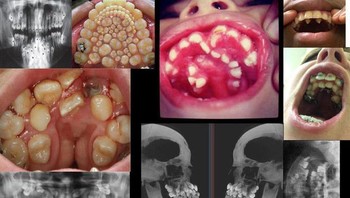

Hyperdontia atau supernumerary teeth adalah kondisi yang membuat pengidapnya mengalami kelebihan gigi di mulut. Foto: Twitter/creepy_org